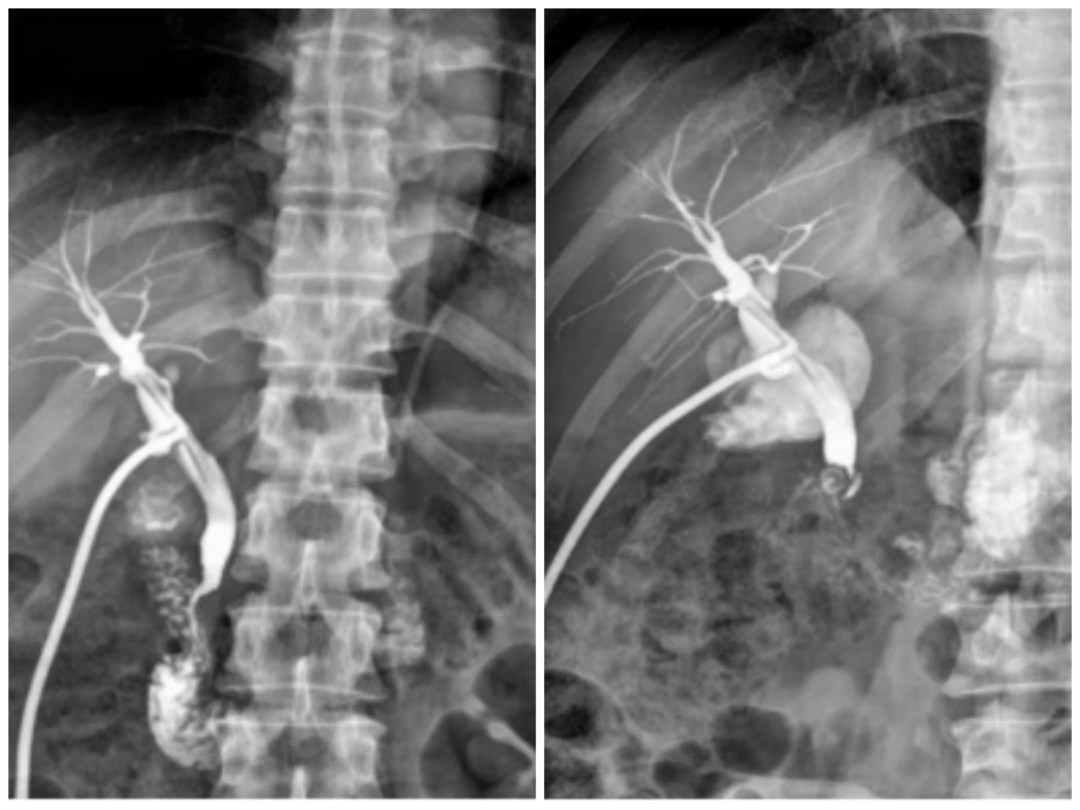

二、特殊检查

包括静脉肾盂造影、逆行肾输尿管造影、子宫输卵管造影、瘘管及窦道造影。